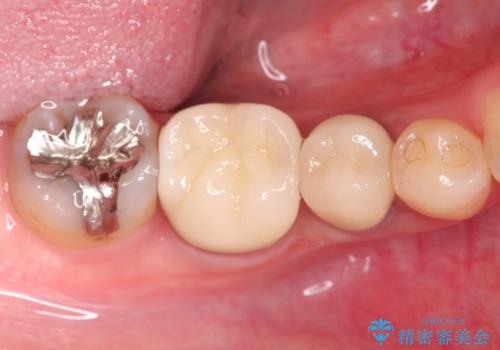

【外部吸収】根管治療、外科治療からのオールセラミッククラウン

根管治療後、外部吸収を認めたため歯周外科を行ない歯冠修復を行なっております。

根管治療後には速やかに歯冠修復が必要です。